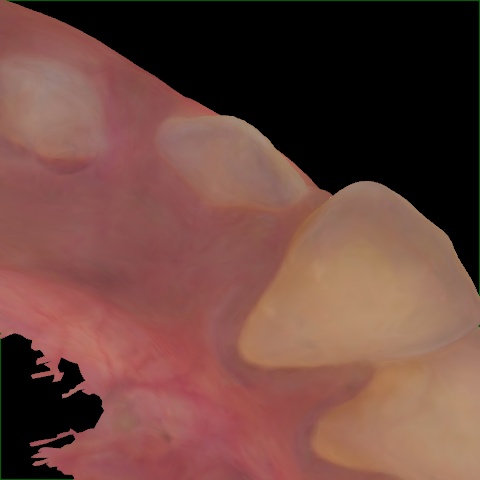

NHD25470

Annotated as "Good"

Original Image Rendering Image